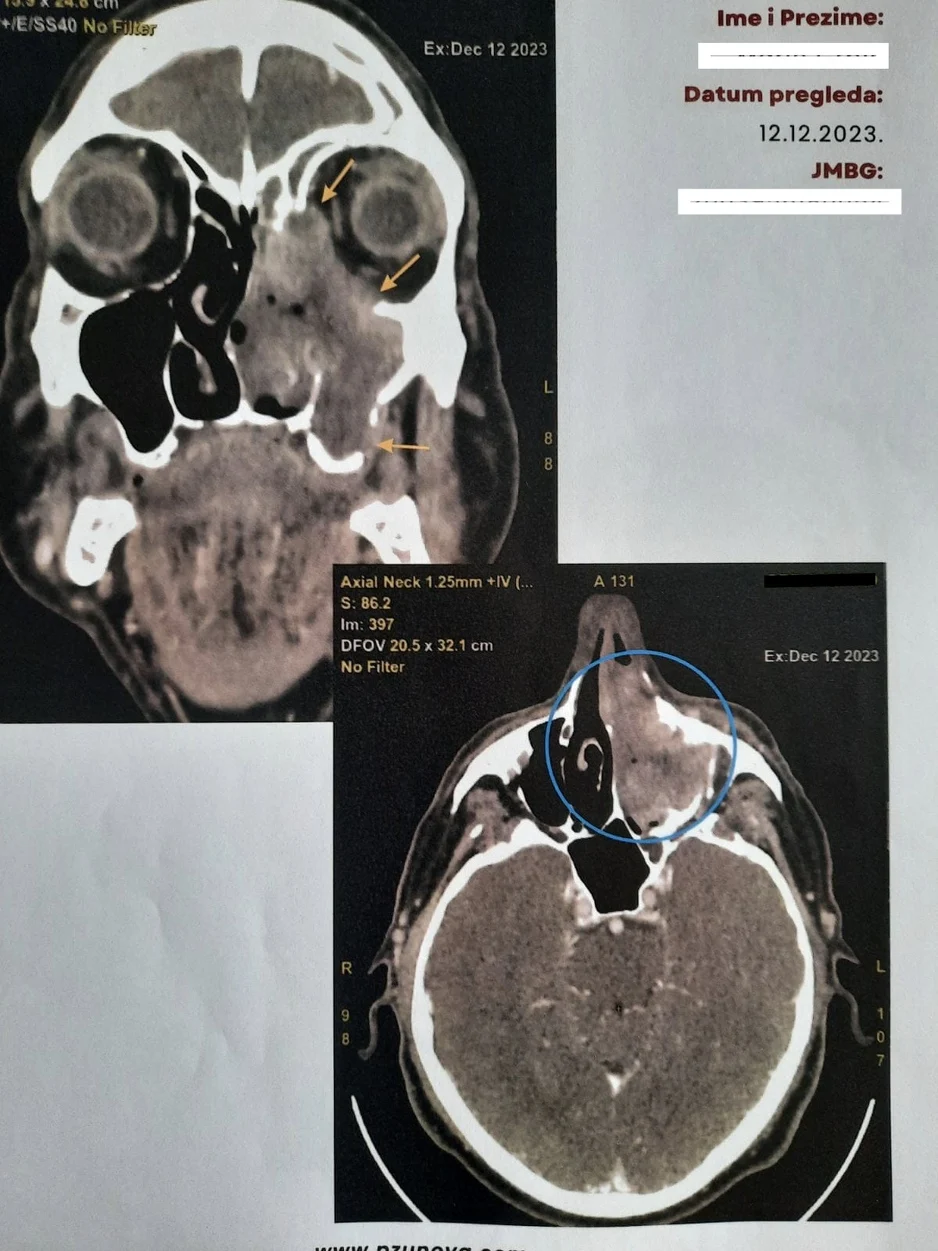

Nedim Leto je na čelu multidisciplinarnog tima, a u razgovoru za Klix.ba je kazao da se ove operacije izvode na teškim onkološkim pacijentima sa uznapredovanim karcinomima glave, lica i vrata.

Dodao je da pacijenti dobivaju kvalitetan tretman u ovoj ustanovi te da je osim uklanjanja tumora jako važna i rekonstrukcija defekta koja se radi lokalnim ili udaljenim režnjevima (deltopektoralni, pektorali, temporalnim mišićem) te slobodnim koštanim graftovima sa kriste ilijake i rebra.

“Na taj način defekt se pokriva u cjelosti i ne izaziva nakaznost postoperativnu nakon radikalnog uklanjanja tumora već pacijent anatomskomorfološki zadržava svoj izgled što doprinosi boljem kvalitetu života postoperativno, ali i omogućava pacijentima lakši i brzi oporavak. Jako je važna i postoperativna njega koja se vrši na Jedinici za intenzivnu njegu uz stalni monitoring i odgovarajući medikamentozni tretman od anesteziologa koji su veoma bitni u ovom čitavom procesu, kao i preostali dio tima”, dodao je Leto.